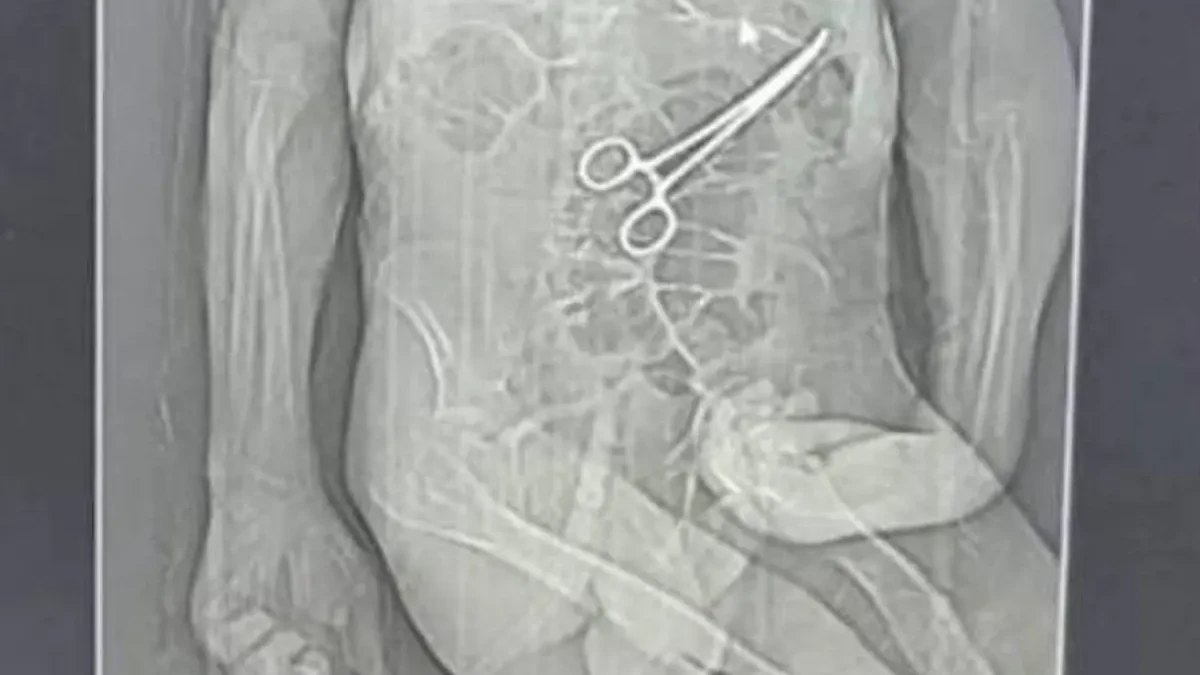

Família acusa hospital de esquecer pinça em corpo de idoso morto (Foto: Reprodução)

Após a cirurgia, o paciente voltou a apresentar sintomas graves, o que levou à realização de novos exames. Nesse momento, uma tomografia identificou, segundo a secretaria, “um corpo estranho na cavidade abdominal”.

Os parentes também afirmam que só souberam do que de fato havia ocorrido por meio de uma reportagem de uma rádio local, quando tomaram conhecimento da imagem de uma tomografia indicando uma pinça no abdômen de Manoel.